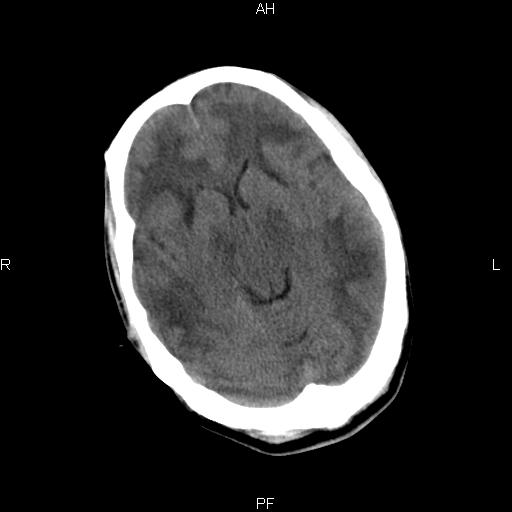

男性,45岁,缄默少语,四肢无力一个月。骨窗未见明确异常。

弥漫性脑白质低密度症

对称性脑白质广泛低密度。有高血压史及大量饮酒史吗?

考虑重度脑白质稀疏症。

双侧弥漫性对称性全累及性(外囊亦有累及)脑白质病

患者病程月余,脑沟裂闭合,第三脑室较窄,提示应该有较明显的脑白质水肿,考虑有持续性炎性病变

综合考虑脑白质感染性或非感染性炎症可能性大,不排除为克雅氏病